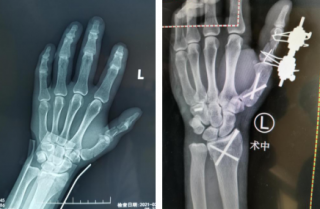

男子被铁器砸伤,左手五处骨折,骨科机器人、腕关节镜同上手术台

男子被铁器砸伤,左手五处骨折,骨科机器人、腕关节镜同上手

术前(左图)术中(右图) 前段时间,家住沛县的张师傅(化名)在自家干活时不慎被铁器砸中左手,当时其左手腕肿胀、畸形。在